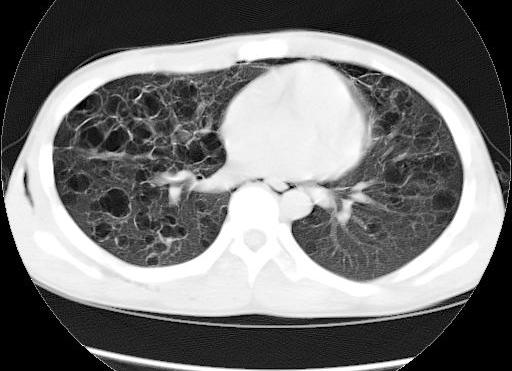

x:双肺中下野多发囊状卷发状影,壁模糊,无液平,双肺纹理强,-------印象:先天支扩并感染.

王某某,男,16岁,既往无经常咳嗽、咳痰、胸闷、发热史,活动与同龄儿童相似,三月前突感胸、颈前痛、无喘憋,查体胸骨上皮下气肿,双肺呼吸音对称。胸部dr及ct示纵隔气肿,双肺囊肿。近两月反复出现胸痛、喘憋,无发热、黄痰及痰血,呼吸音减低,胸部dr示双侧自发性(张力性)气胸,胸腔闭式引流治愈。频繁发作,左侧引流两次,右侧引流三次。

1.诊断考虑先天性肺囊肿(囊性肺),自发性、张力性气胸,鉴别支气管扩张,先天性囊性腺瘤样畸形等

从上述x线片、ct片看,先考虑先天性肺囊肿(囊性肺),伴气胸、纵隔积气、皮下积气;先天性囊性腺瘤样畸形,一般中叶很少累及.

先考虑先天性肺囊肿(囊性肺),伴气胸、纵隔积气、皮下积气,胸水.先天性囊性腺瘤样畸形